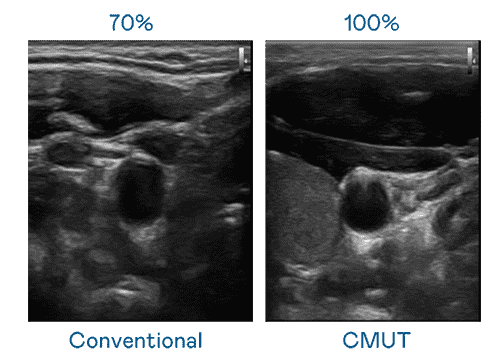

CMUT 技术是一种用电容式微机电元件来产生超音波讯号的技术。。。与传统 PZT 压电式技术相比,,CMUT 频宽增加 30%,,更宽频的超音波讯号让影像解析度大幅提升,,,是实现高影像品质医疗超音波扫描、、、、促进精准医疗发展的关键技术。。

大频宽带来超清晰影像

超音波影像的解析度高低,,,首先取决于探头能发出的讯号频宽。。。。汇旺支付 CMUT 可提供高清晰的超音波讯号,,提供高频宽、、、、高灵敏度、、、影像纹理细节更高的超音波影像,,,协助医护人员缩短影像判读时间及利用精准的医疗影像进行诊断。。。。